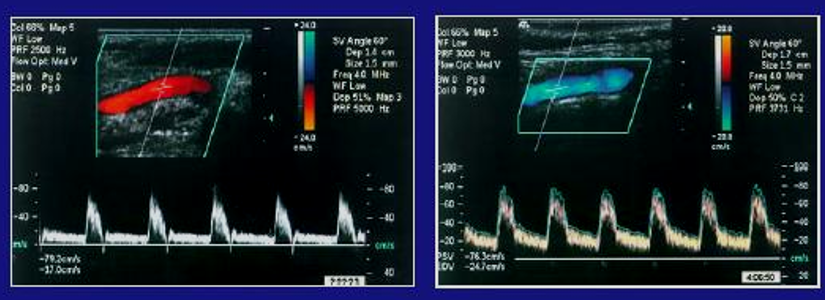

Based on the waveforms, Which vessel do they belong to?

ICA

True or False: The picture on the right shows a vertebral flow pattern

False

True or False: The picture on the right shows an ICA flow pattern

True